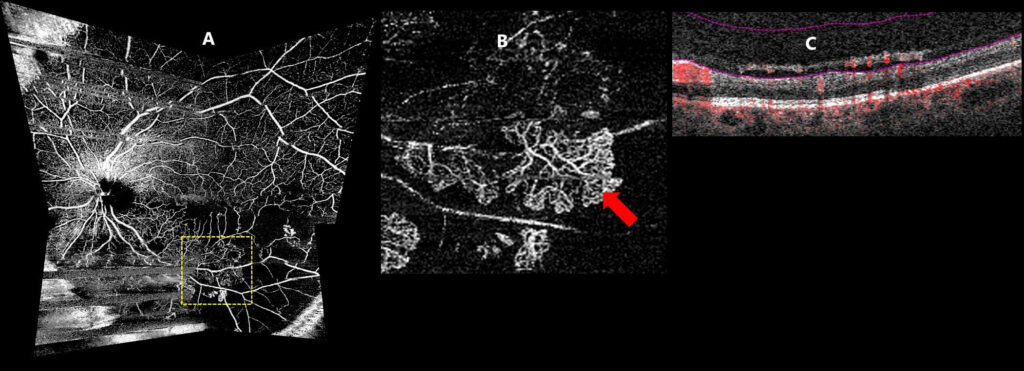

Figure 4. Optical coherence tomography angiography (OCT-A) at 2-year follow-up. A) En-face montage OCT-A imaging of the superficial vascular plexus (internal limiting membrane to inner plexiform layer) showing extensive retinal non-perfusion (greater than 10-disc areas) within the inferior retina. Several motion artifacts can be seen which decreases image quality. B) En-face OCT-A of the vitreoretinal interface (300 µm anterior the internal limiting membrane to internal limiting membrane) showing several pre-retinal neovascular membranes (red arrows). The area of B is denoted by the yellow box in A. C) Co-registered OCT B-scan showing pre-retinal neovascularization. Automated software segmentation of the vitreoretinal interface is shown in pink. Red overlay corresponds to OCT-A flow signal.

OCT imaging revealed inner retinal thinning and disorganization, particularly within the inferior macula. The outer retinal layers and the ellipsoid zone appeared intact, with no macular edema (Fig. 3). Pre-retinal neovascularization was noted along the posterior hyaloid face at the inferior temporal arcade. This was confirmed by OCT-A (Fig. 4).

Wide-field OCT-A imaging allows for thorough evaluation of overall retinal blood flow and shows excellent agreement with fluorescein angiography.39 Wide-field OCT-A images are generally obtained using a panoramic montage by combining images taken in several gazes including central, superior-nasal, superior-temporal, inferior-nasal and inferior-temporal, typically using a large scan size such as 8×8 mm or 12×12 mm.39 Clinicians should examine both the SCP and DCP to evaluate capillary dropout and retinal non-perfusion.39 This can be used to identify ischemic CRVOs and assess risk of neovascular sequelae by determining the extent of retinal non-perfusion.39 Similar to fluorescein angiography, retinal non-perfusion seen in the SCP and DCP of 10 disc areas or more in the posterior pole can be used to define ischemic CRVO.39,42 Additionally, wide-field OCT-A imaging is useful to identify retinal neovascularization.43 To detect preretinal neovascularization, clinicians should examine the vitreoretinal interface, the area anterior to the internal limiting membrane.43 Flow signal detected at the level of the vitreous is characteristic of retinal neovascularization (Fig. 4C).43